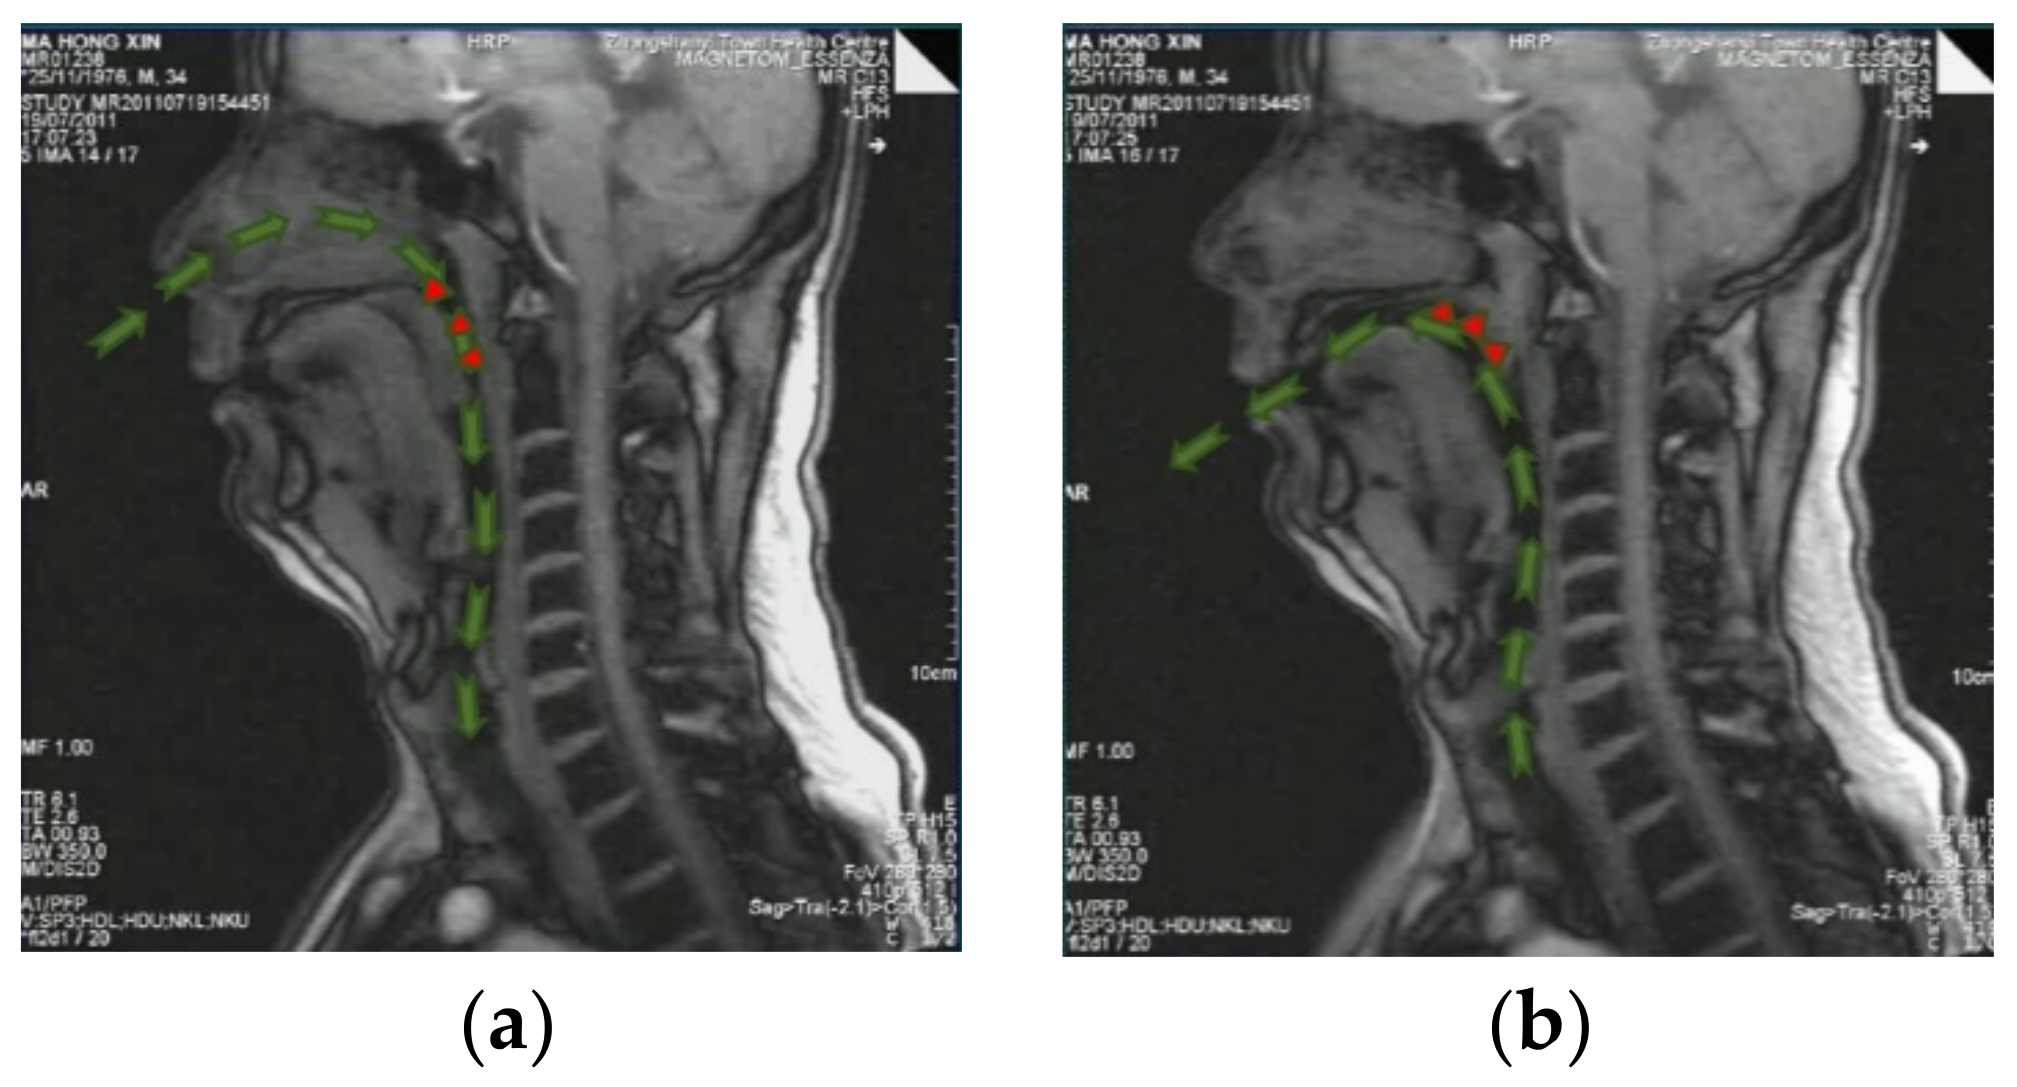

When a patient with OSAHS inhales through the nose, air flows through the valve area and causes snoring. During the expiration phase, the valve area in the soft palate would be closed, and hence, there is no nasal passage for the exiting airflow and the air is forced to exit from the mouth. In our experiment, the one-way valve effect of an OSAHS patient was clinically observed by means of high-speed dynamic MR, as shown in Figure 6.

Figure 6.

One-way valve effect of an OSAHS patient. (a) Act of inhaling; (b) exhaling. Green arrows indicate the airflow path.